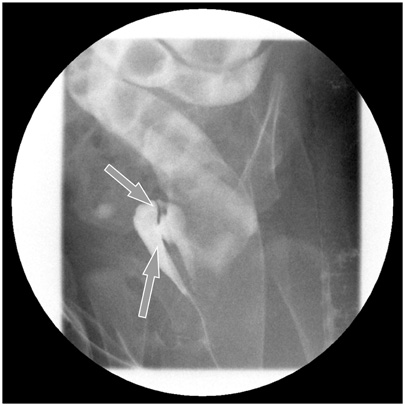

Fig. 1). Under general anesthesia, a small opening located posterior to and near the vagina at vestibule was found. The structure that had been misdiagnosed as a fistula based on the colon study was not present. The patient had a normally sited anus, an anterior ectopic anus, and a double vagina (

Fig. 2). A catheter was inserted through the ectopic anus, and an intraoperative contrast study and sigmoidoscopy were performed. A parallel tubular duplication with a common wall was found. The common wall extended 5 cm from the anal verge to the sigmoid colon and then 20 cm to the level of the proximal sigmoid colon. Proximally, the anterior duplication and normal colon merged and formed a normal colon. Because most of the stool moved through the anterior duplication and because the diameter of the anterior duplication was larger than that of the normally located colon (

Fig. 2Examination under general anesthesia revealed a normal anus, an anterior anorectal duplication (catheter-inserted state), and duplicate vaginal openings.